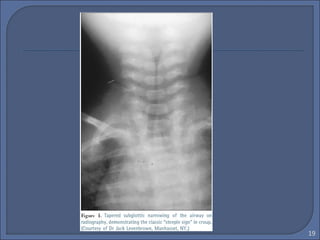

• Laringotracheitis :“ The Steeple

Sign”

• Epiglottitis : “ Thumb Sign”

 CXR : Plain film of the neck

• Steeple sign

• Overdistended hypo pharynx( lateral)